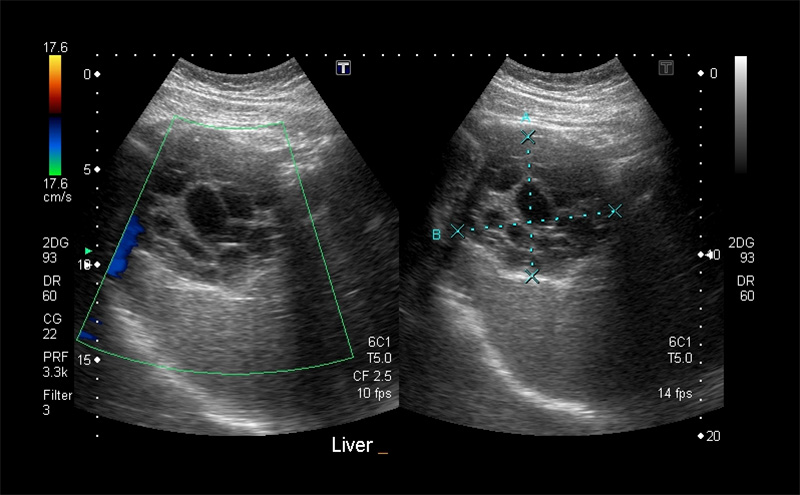

Figure 11. Normal Liver as seen from the right flank coronal view. Note the smooth surface, fine homogenous texture, and tubular vascular structures. The normal anterior-posterior diameter in the mid-clavicular line sagittal plane is between 12-14cm (A). The normal maximum dimension is from anteroinferior to posterosuperior is <16cm (B).